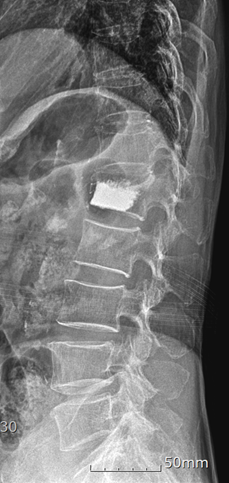

74세 어머님(A씨)이 화분을 들여 놓다가 허리에서 뚝소리가 났고, 요통이 발생하여 내원했다. X-ray 검사를 해보니 제1번 요추 추체가 주저 앉아 다른 부위에 비하여 좁아져 있었다. 추체 압박 골절이 된 것이다. 주사치료 약물치료등을 시행하였는데도 증상의 호전이 없어 뼈시멘트 주입술을 시행 후 다음날 보조기 차고 퇴원을 하셨다. 골절 원인은 다름아닌 '골다공증'이었다. 과거에 어머님도 골밀도 검사를 통해 골다공증이 있다는 진단을 받았지만 "그냥 우유랑 멸치만 먹으면 되겠지" 라는 생각으로 지내오셨다. 식이요법만으로 되겠지 했던걸 많이 후회하신다고.

A씨는 골다공증을 간과하다가 결국 척추 보조기를 3개월 차고 뼈에는 골시멘트 주입하는 시술을 받게 되었다.

![골시멘트 주입 수술 후 사진. [자료=나누리병원]](https://img4.daumcdn.net/thumb/R658x0.q70/?fname=https://t1.daumcdn.net/news/202411/29/KorMedi/20241129155510420uwkt.png)